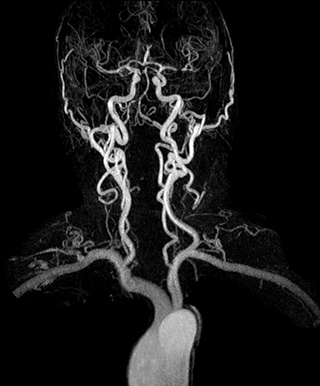

“In our peripheral MRA run-off studies with Ambition we realize key benefits, including outstanding image quality and significantly reduced breath-hold and scan times, which not only benefit the patient, but also provide the opportunity to add sequences that could aid in diagnosis,” Dr. Peña says.

“Before we had Ingenia Ambition, our CE-MRA run-off studies would first acquire a dynamic pre-contrast scan with 20-25-second breath-holds, then inject the contrast, do another acquisition and then subtract the two,” says Avila. “Now, mDIXON XD allows us to complete the study in just one single pass – without need for a pre-exam – which eliminates subtraction artifacts and almost halves the scan time. In addition, mDIXON provides much better background suppression, which really improves vesselto-background contrast. And, thanks to Compressed SENSE, the single breath-hold is not long and we improve image resolution.”

The subtractionless peripheral MR angiography shows improved vessel-to-background contrast and high resolution. Ingenia Ambition 1.5T.

| Station | Ingenia Ambition |

| Pelvis | Voxels 1.3 x 1.3 x 3.2 mm, FOV 430 mm, 125 slices |

| Upper legs | Voxels 1.3 x 1.3 x 3.2 mm, FOV 430 mm, 125 slices |

| Lower legs | Voxels 1.0 x 0.82 x 2.0 mm, FOV 430 mm, 125 slices |

The time saved by Compressed SENSE and mDIXON XD is sometimes used to include additional sequences. An example are peripheral MRA studies, in which Compressed SENSE and mDIXON XD help achieve a 5- to 10-minute reduction in scanning time. This brings the total time down, from the 45 minutes needed with their previous system to about 30 to 35 minutes on Ingenia Ambition, thus providing ample time to include additional sequences.

“These scans are so fast now that we have been able to add a non-contrast MRA sequence within the same timeslot. We compare the respective image quality with the goal to determine whether the non-contrast sequence could be an alternative for patients who can’t tolerate gadolinium contrast agents due to poor kidney function,” says Avila. “We find the image quality of the non-contrast sequence so good that we can now also offer peripheral MRA to these patients whom we had been unable to serve before Ambition, so that has been great.”